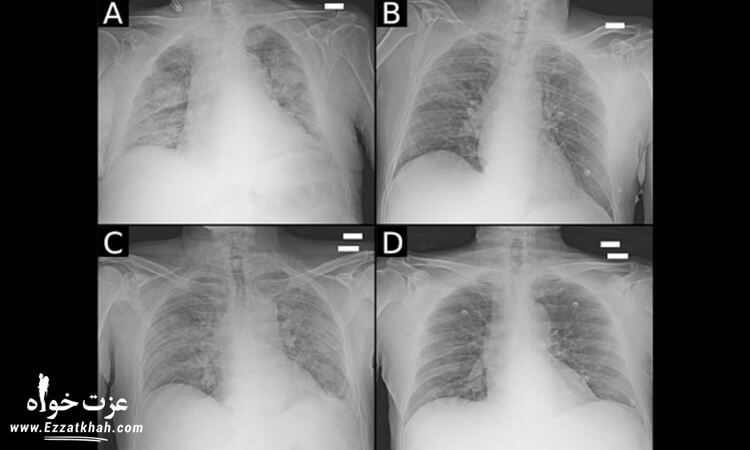

« ما شاهد تحولی عظیم در نحوه تشخیص بیماری در طول یک سال اخیر بوده ایم، از تجزیه و تحلیل تصویری ایکس ری با دستگاه های خود آموز گرفته تا توسعه در سرعت و کیفیت کیت های تشخیص بیماری که مستقیماً به دست مشتری می رسند، » به نقل از دکتر وین گوپتا، پزشک سرپرست تیم واکنش به کووید 19 آمازون.

برنامه توسعه تشخیص دهی AWS باعث سرعت بخشی به پروژه هایی شده است که تأثیر مستقیمی بر تشخیص کووید 19 داشته اند، در همین راستا اقداماتی که با تشخیص پزشکی ممکن هستند، به کلی متحول شده اند.

این پروژه ها تنها در حال کمک به جوامع پزشکی در مبارزه با کووید 19 نیستند، بلکه به توسعه و تحقیق در دیگر بیماری های واگیردار نیز کمک می کنند. در زیر به تعدادی از پروژه هایی که توسط برنامه توسعه تشخیص دهی AWS حمایت شده اند، اشاره شده است: